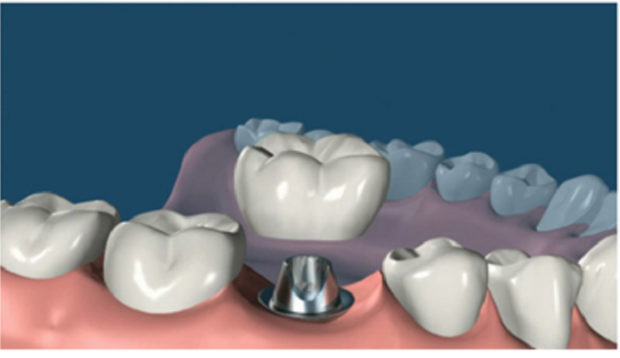

6. 安裝基臺(tái):骨愈合后就可以進(jìn)行二期手術(shù)使種植體穿出牙齦,為了幫助牙齦軟組織更快的愈合,會(huì)通過手術(shù)把種植體的覆蓋螺釘取替換成愈合螺釘。

7. 覆蓋義齒:兩至三周待軟組織成型后,就可以把愈合基臺(tái)換成基臺(tái)佩戴種植牙冠了;至此種植牙全部流程都已全部完成。